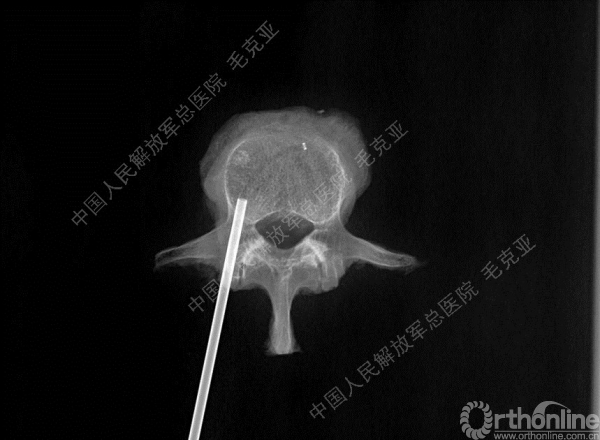

导语:随着社会老龄化的不断加速,骨质疏松性椎体压缩骨折作为一种普遍存在的老年骨科疾病已经成为现今骨科界的一个热点话题。传统的保守疗法治疗效果不佳,而现有的椎体增强技术又具有多种风险和缺陷。针对这种现状,中国人民解放军总医院毛克亚教授提供了一种新的解决方法。